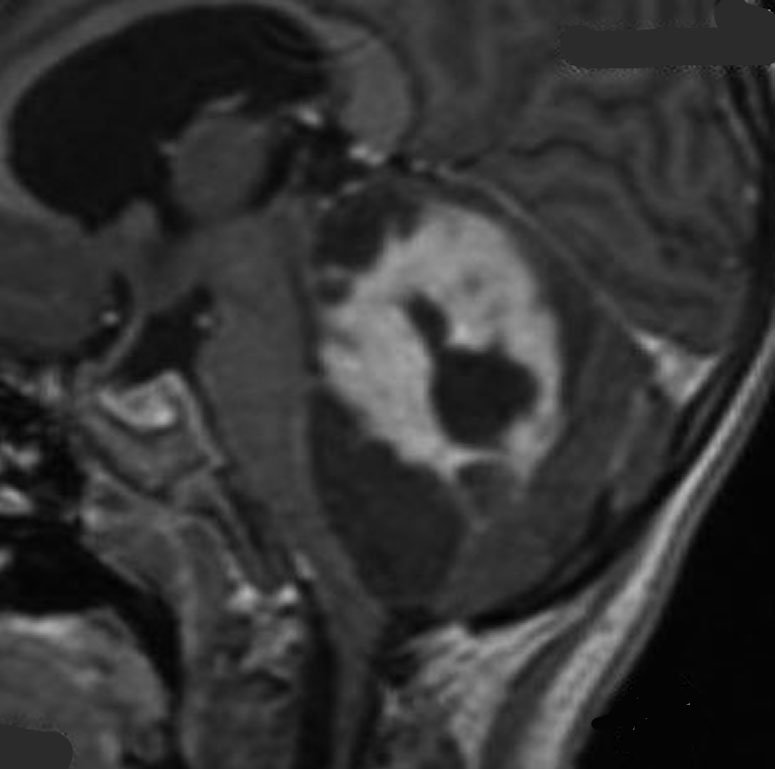

同じような小児例です

右側は手術直後のFLAIR像です。小児ですから大きなのう胞はすぐに潰れて小脳がもどります。白質損傷もなく腫瘍は摘出できています。

これも小脳中部上端から発生したもので,中脳水道が開いています。OTAで摘出しなければ小脳中部に大きな損傷を与えるものですから,後頭下開頭をしてはなりません。術後10年ほど経ちますが再発はなくてダンスをしてます。